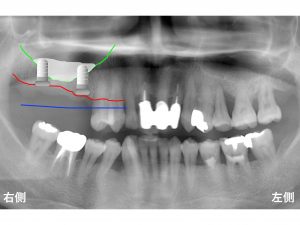

以下が初診時です。

上顎右側の奥歯が3歯欠損しています。

本来歯を支えていた骨は、

以下の青線 まであったのです。

それが骨が溶けて(吸収して)しまったのです。

以下の赤線 までです。

青線 から

赤線 まで骨吸収したのです。

さらに問題となったのが

上顎洞 の存在です。

上顎洞 は、

上顎の奥歯の上方にある空洞のことです。

欠損部の手前側は、

ある程度の骨の高さはあります。

しかし、

その奥になると急激に骨の高さが少なくなります。

一番奥歯も骨の吸収が起こっています。